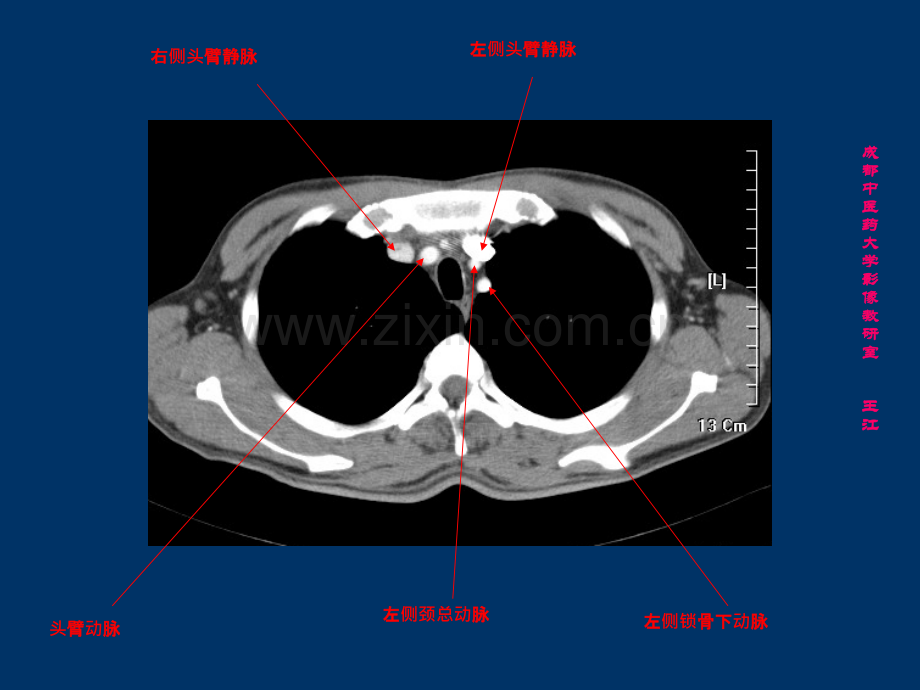

右右侧头臂静脉臂静脉左左侧头臂静脉臂静脉左左侧颈总动脉脉左左侧锁骨下骨下动脉脉右右侧颈总动脉脉右右侧锁骨下骨下动脉脉成成都都中中医医药药大大学学影影像像教教研研室室王王江江右右侧头臂静脉臂静脉左左侧头臂静脉臂静脉左左侧颈总动脉脉左左侧锁骨下骨下动脉脉头臂臂动脉脉成成都都中中医医药药大大学学影影像像教教研研室室王王江江左右左右侧头臂静脉臂静脉汇合区合区胸腺胸腺主主动脉弓脉弓成成都都中中医医药药大大学学影影像像教教研研室室王王江江上腔静脉上腔静脉气管气管食道食道奇静脉奇静脉成成都都中中医医药药大大学学影影像像教教研研室室王王江江左肺左肺动脉脉升主升主动脉脉降主降主动脉脉上腔静脉上腔静脉右主支气管右主支气管左主支气管左主支气管成成都都中中医医药药大大学学影影像像教教研研室室王王江江肺肺动脉主干脉主干左肺左肺动脉脉右肺右肺动脉脉上腔静脉上腔静脉成成都都中中医医药药大大学学影影像像教教研研室室王王江江右下肺右下肺动脉脉左下肺左下肺动脉脉升主升主动脉根部脉根部左心房左心房右心耳右心耳成成都都中中医医药药大大学学影影像像教教研研室室王王江江左心房左心房右心房右心房右肺静脉右肺静脉左肺静脉左肺静脉成成都都中中医医药药大大学学影影像像教教研研室室王王江江左心房左心房右心房右心房右心室右心室左心室左心室降主降主动脉脉成成都都中中医医药药大大学学影影像像教教研研室室王王江江降主降主动脉脉下腔静脉下腔静脉食道食道成成都都中中医医药药大大学学影影像像教教研研室室王王江江隔隔顶奇静脉奇静脉食道食道下腔静脉下腔静脉成成都都中中医医药药大大学学影影像像教教研研室室王王江江膈肌脚膈肌脚成成都都中中医医药药大大学学影影像像教教研研室室王王江江